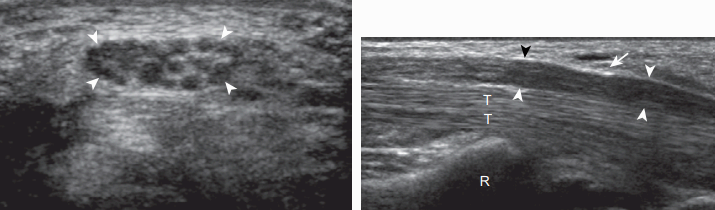

자뼈굴증후군(ulnar tunnel syndrome) 은 기욘굴 내의 자신경이 눌리는 죄임신경병증으로 외상이 가장 흔한 원인이다. 갈고리뼈의 갈고리 부위가 자신경과 자동맥 깊은 곳에 있기 때문에 손안쪽에 직접적 충격이 가해질 때 자신경과 동맥에 손상을 줄 수 있다. 이러한 경우에 자신경의 타박상 또는 자동맥류에 의한 자신경 압박이 생기거나 자동맥 혈전증 등과 관련되어 자뼈굴 내에 부종이 생길 수 있다. 초음파에서 자신경은 낮은 에코로 보이고 탐촉자로 압박하면 자신경이 탐촉자와 갈고리뼈의 갈고리 사이에서 압박되어 증상이 재현된다. 초음파로 갈고리뼈의 갈고리를 찾기 위해서는 콩알뼈의 바로 아래 안쪽에 시상면으로 탐촉자를 놓으면 된다. 자동맥류는 자동맥과 연결되는 불균질 한 덩어리로 보이고, 색 및 강화도플러 영상에서 왕복운동 (to-and-fro, yin-yang)에 의한 혈류가 보이지만, 혈전이 있으면 혈류가 보이지 않을 수 있다. 이와 관련된 질환으로 새끼두덩갈고리뼈증후군(hypothenar hamate syndrome) 이 있으며, 자동맥 외상에 의한 자동맥류 또는 혈전증과 함께 손가락 쪽의 색전(emboli)에 의한 혈관 부전증(vascular insufficiency)이 초래된다.